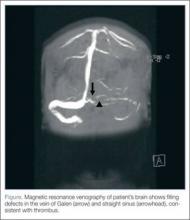

Based on the patient’s history of ET and postpartum state, there was a high suspicion for cerebral venous thrombosis (CVT). Magnetic resonance imaging/magnetic resonance venography (MRI/MRV) of the brain was obtained, which revealed near-complete thrombosis of the vein of Galen and straight sinus (Figure). Neurology and hematology services were consulted emergently, and the patient was started on a heparin drip and admitted to the neurosurgical intensive care unit. Hydroxyurea was also given for cytoreduction, and platelets normalized to 305 x 109/L within 1 day of treatment. The patient’s neurological examination remained nonfocal, her headache gradually resolved, and she was discharged on hospital day 3 on oral anticoagulants.